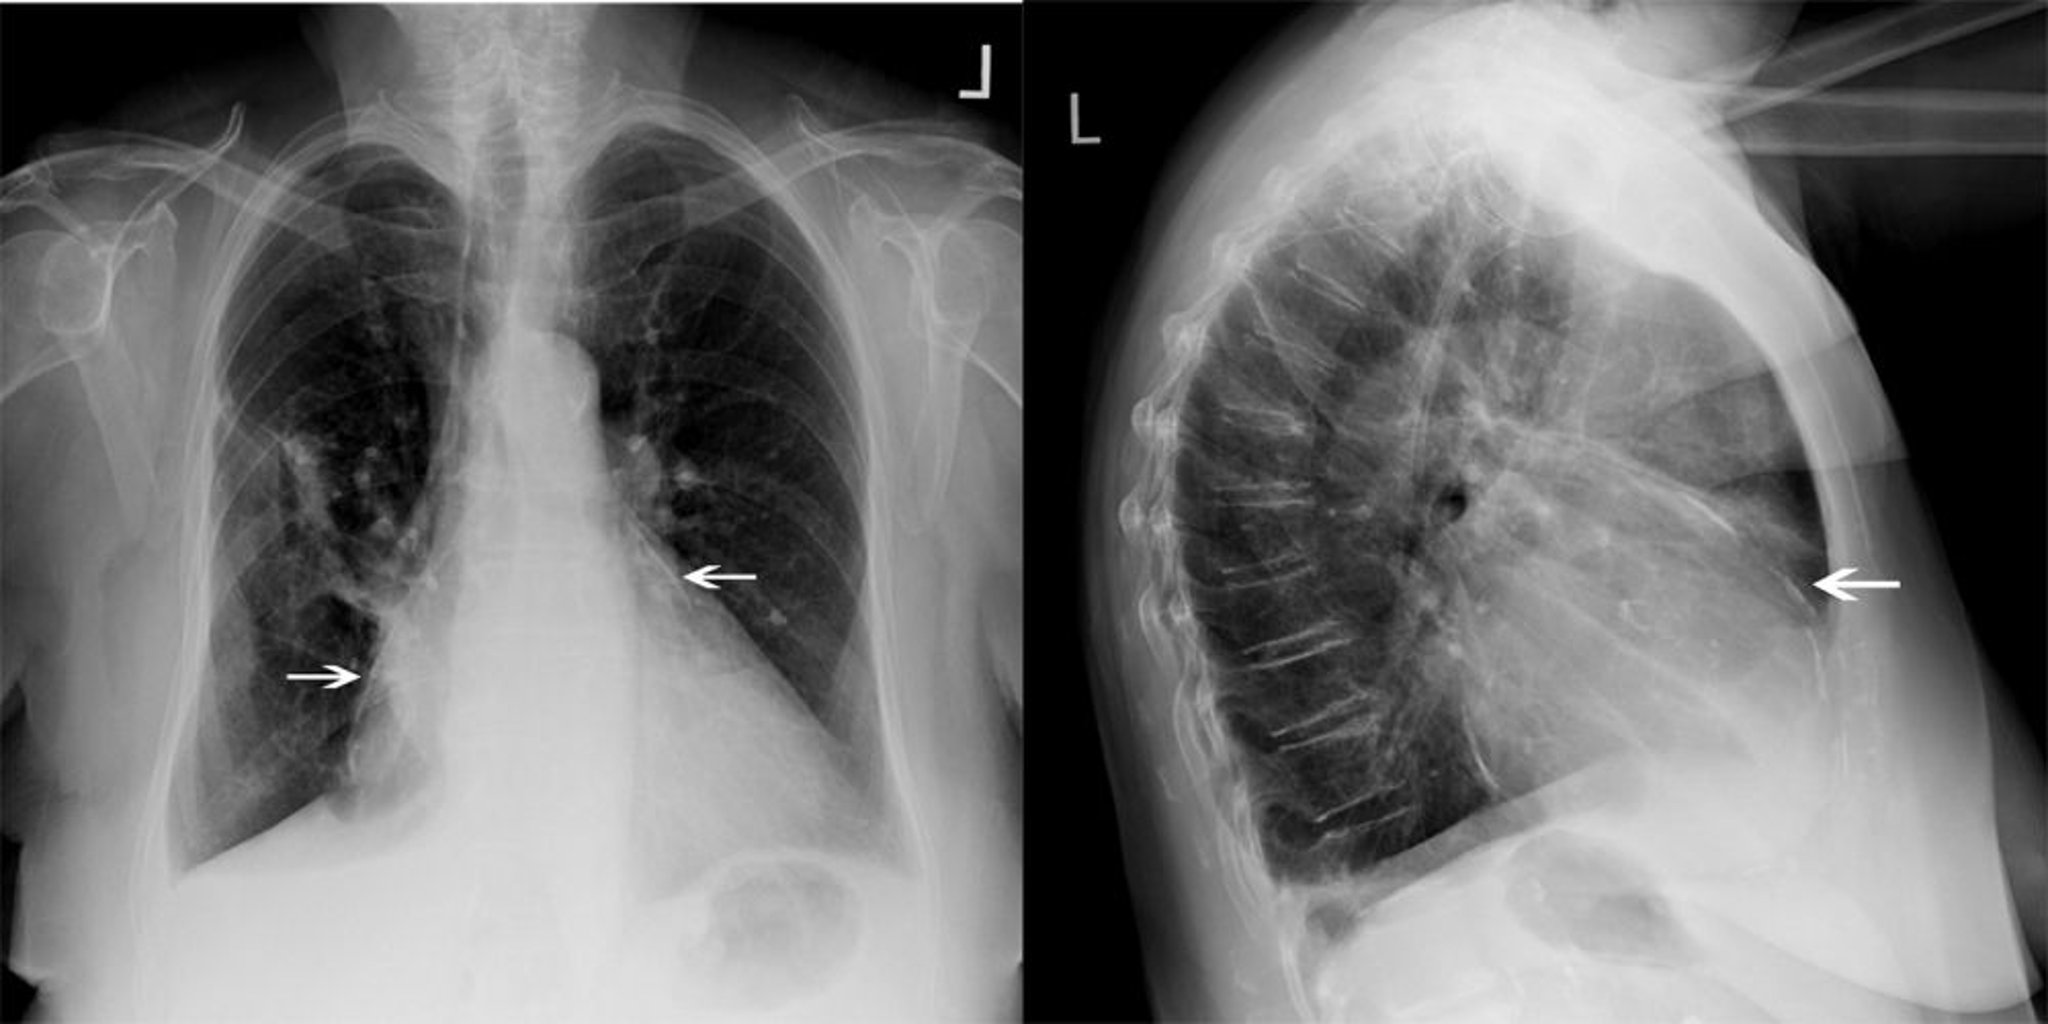

Röntgenthorax eines Patienten mit konstriktiver Perikarditis

Dieser Patient mit konstriktiver Perikarditis weist eine deutliche Perikardverkalkung auf (weiße Pfeile).